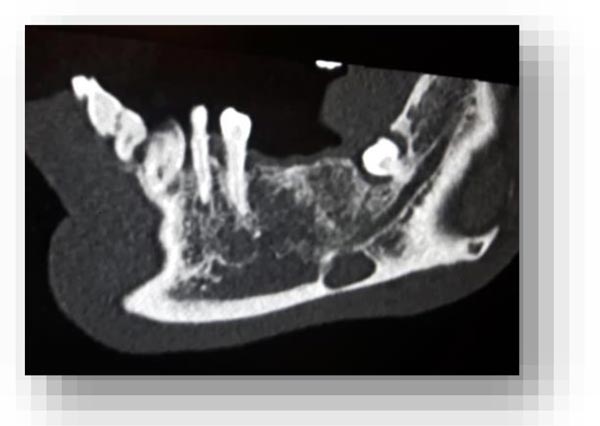

In this radiographic exam, we found an oval notch with radiolucent, clear and regular borders, located in the inferior portion of the horizontal branch of the mandible, on the lingual side, near the angle of the mandible, and below the mandibular canal. The X-ray allowed precise measurement showing a height ranging between 13.5 mm and 17 mm and breadth between 6 and 8 mm (Figs. 4-5).

The bi-dimensional reconstructions in parasagittal slices also permitted better identification of the closeness of the bone cavity to the canal of the alveolar inferior omolateral nerve, whereas the computerized volume rendering offered a more accurate view of the surrounding anatomical features (Figs. 6-12).